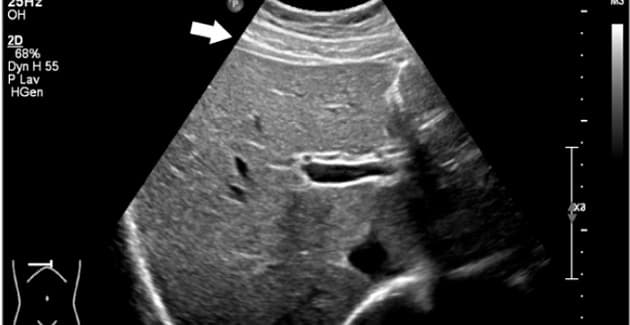

UL skanningsbillede af patientens lever.

Fitz-Hugh-Curtisʼ syndrom (FHCS) er en komplikation til underlivsinfektion og giver perihepatitis med smerter under højre kurvatur. Kasuistikken af Skov og Schreiber beskriver sygdomsforløbet hos en tidligere rask 21-årig kvinde og anfører, at et karakteristisk fund er fortykket og trelaget leverkapsel på UL-skanningsbilledet.